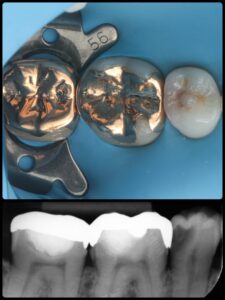

虫歯が深くても、神経を残せる可能性があります!

当院では、歯の寿命を左右する「神経」を可能な限り保存する治療に取り組んでいます。

✅ 神経が露出しても諦めない保存処置

✅ 再発リスクを抑える精密治療

✅ 自費治療ではラバーダム防湿を徹底(無菌的処置)

「神経を抜くしかない」と言われた場合でも、保存できるケースがあります。大切な歯を守るためのベストな選択肢を一緒に考えましょう。